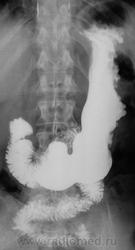

Лежа бы вниз головой... Ну а так, дефект наполнения по большой кривизне свода. М.б. что угодно, больше за гиперплазию или онко.

Тугое заполнение свода + можно пасс. рефлюкс, или не там патологию вижу? Просто стол опустить с пациентом ( который стоя стоит) на 10-15градусов без вычурных.

Почему не локальная форма Менетрие?....

"Картинка" то типичная, именно, для болезни Менетрие.

Менетрие? По одному снимку, без второй порции бария, без шипучки и снимков в горизонтальном положении. Как-то лихо.

Спасибо за интересное наблюдение, Валентин Львович! Если есть возможность покажите пожалуйста все рентгенограммы выполненные в процессе исследования.